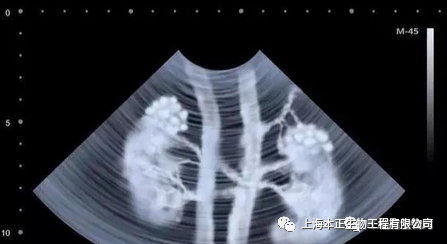

【本正干细胞】有效修复肾细胞,恢复肾功能

干细胞修复肾脏功能

近年来干细胞治疗肾病过程中发现,干细胞可分化成肾固有细胞,肾实质细胞等,干细胞治疗对肾脏功能具有良好的修复和重建作用。

因为干细胞治疗可以修复受损肾细胞,避免肾功能的完全丧失改善并发症,延缓肾脏衰竭进程,提高生存质量。